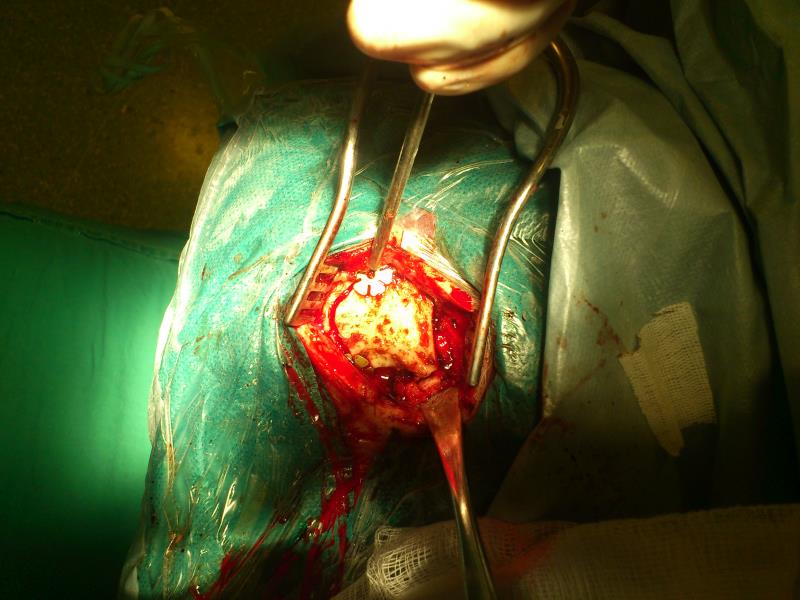

Ασθενής   55 ετών  ο οποίος είχε υποβληθεί  προ 3μήνου σε ενδοσκοπική διασφηνοειδική αφαίρεση μακροαδενώματος υπόφυσης  ( αδύνατη λόγω σκληρής σύστασης του όγκου η αφαίρεση του υπερεφιππιακού τμήματος του όγκου) προσήλθε στην κλινική μας  με σκοπό την αφαίρεση  του υπερεφιππιακού τμήματος του όγκου  δια υπερόφρυας τομής δέρματος και δεξιάς mini orbitozygomatic keyhole approach.  Η μετεγχειρητική του πορεία ήταν ομαλή με περαιτέρω βελτίωση των οπτικών του πεδίων ( αρχική μικρή  βελτίωση μετά την ενδοσκοπική διασφηνοειδική προσπέλαση ) και ο απεικονιστικός έλεγχος ανέδειξε την πλήρη αφαίρεση του υπολειμματικού όγκου.

1. Ήπια έλξη του δεξιού μετωπιαίου λοβού , διάνοιξη  οπτικοκαρωτιδικής δεξαμενής, έξοδος ΕΝΥ και βελτίωση διεγχειρητικών συνθηκών.

2. Dissection επί τα έκτος της έσω καρωτίδος και αναγνώριση – ανάδειξη του κοινού κινητικού νεύρου (carotidooculomotor triangle).

3. Αναγνώριση της κάψας του όγκου επί τα έσω του δεξιού οπτικού νεύρου στο interoptic space.

4. CUSA και debulking του όγκου. Παρασκευή του αραχνοειδούς πλάνου του όγκου.

5. Ανάγνώριση αριστερής Α1 και εντυπώματος ( indentation)  που προκαλεί στο αριστερό οπτικό νεύρο.

6. Αφαίρεση του όγκου και αναγνώριση αριστερής έσω καρωτίδας και του υπερκείμενου αριστερού οπτικού νεύρου.